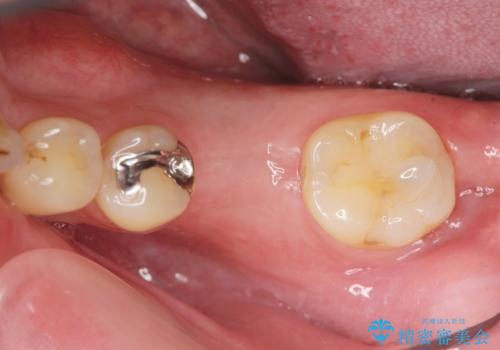

- 銀歯の奥歯で噛むと違和感・痛みがあるとのことで検査・治療を求めて来院されました。

銀歯を除去して見ると内部で虫歯が再発し、歯の辺縁は破折し保存が難しく抜歯をしなければいけない状態でした。

抜歯後ブリッジとインプラント治療を検討・相談し、より周囲の歯を削らずに済むインプラント治療を希望されたのでインプラントによる機能回復を計画します。